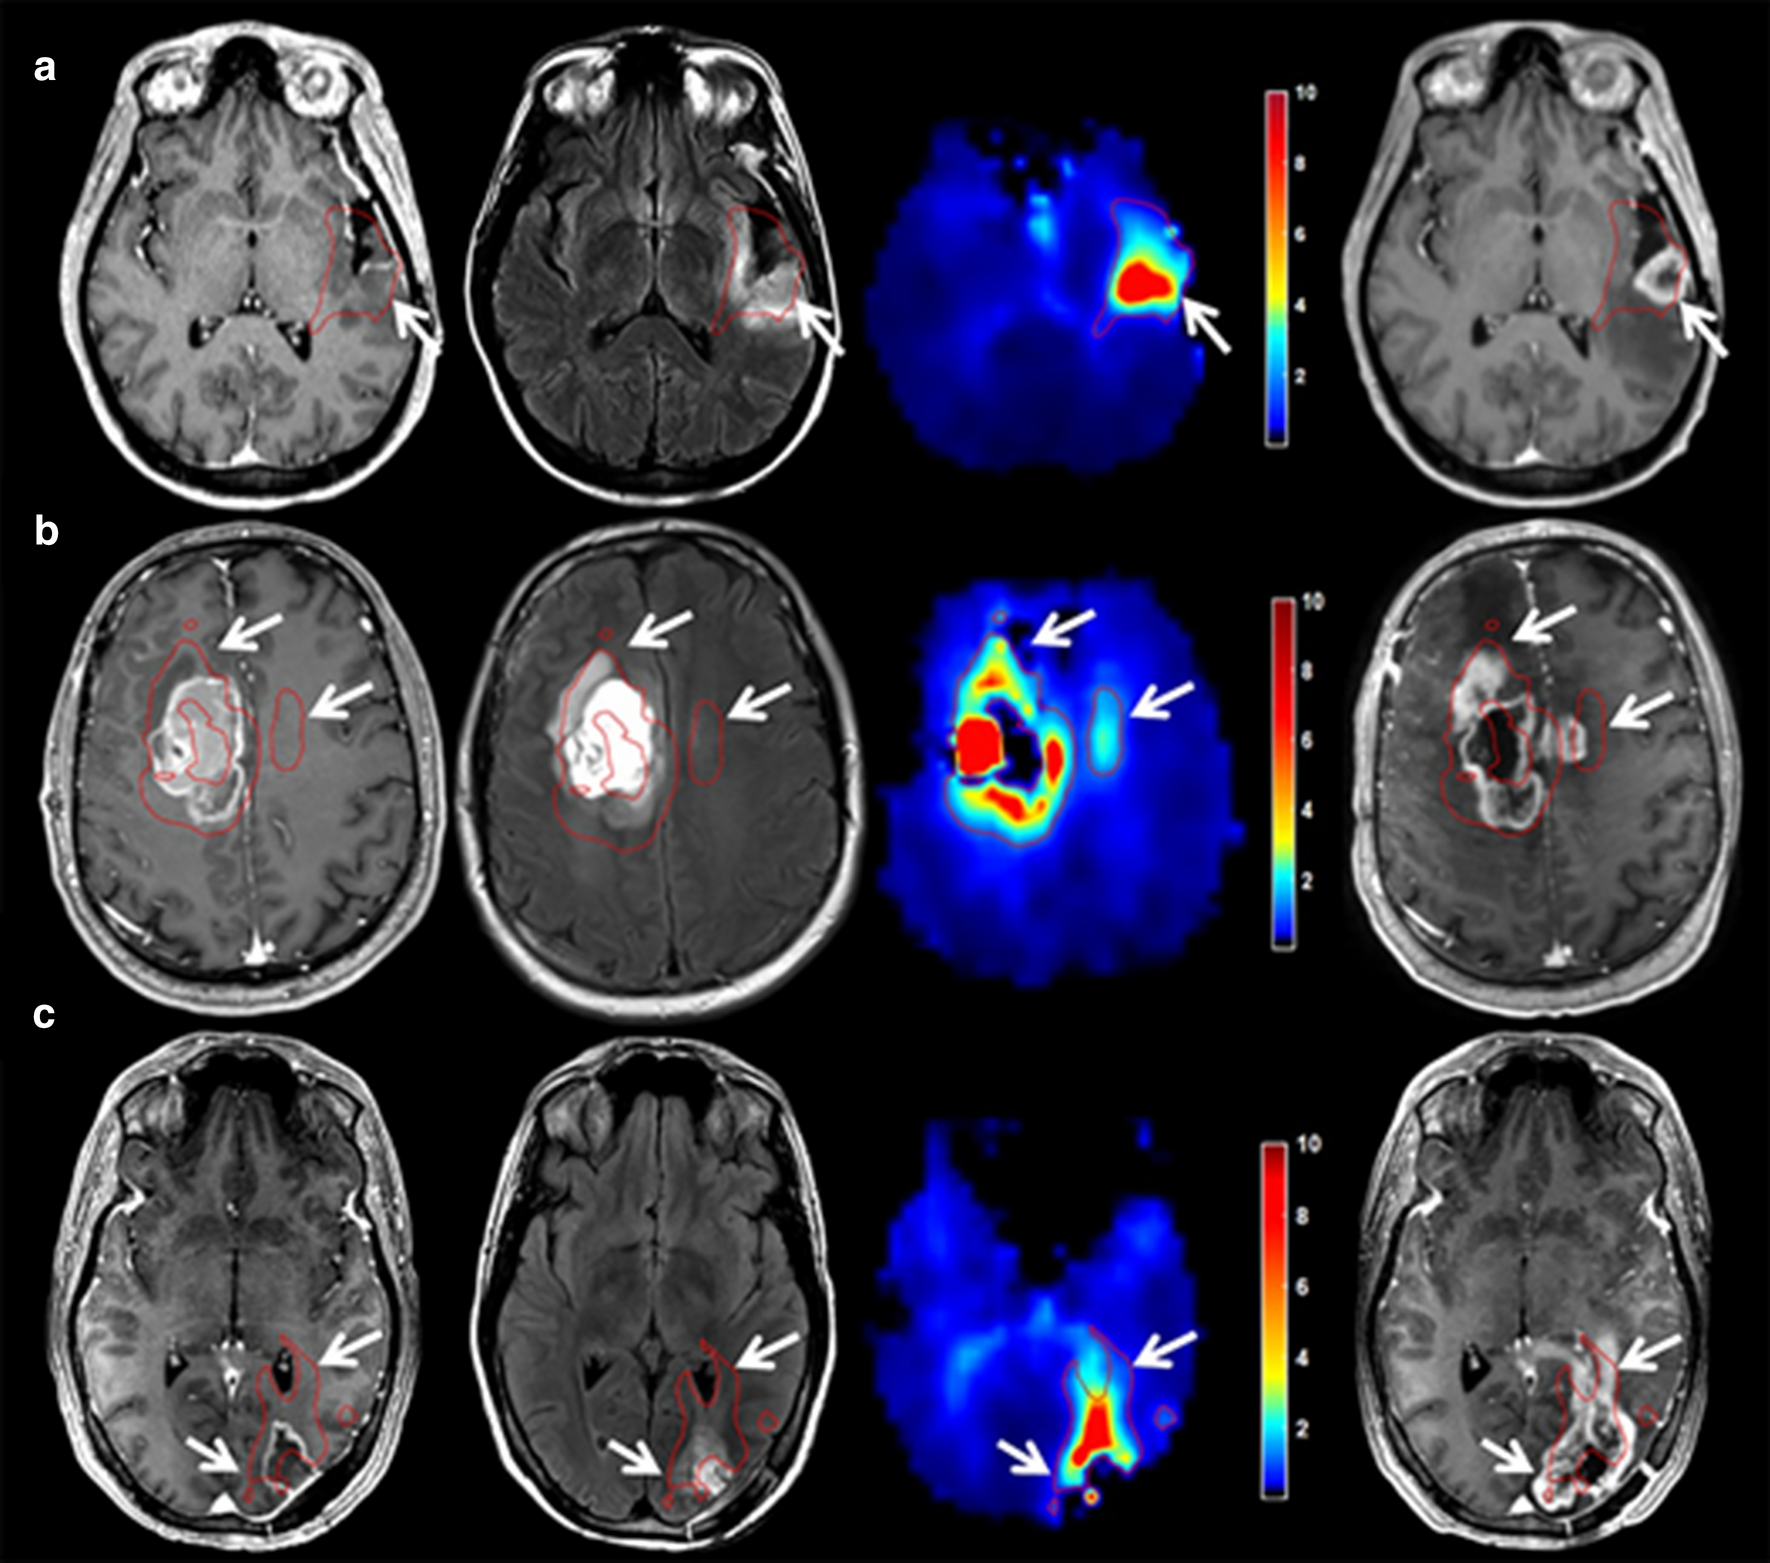

In addition to the correlation with tumour infiltration, various studies have shown that increased rCBV can be an indication for high-risk regions of future relapse. Stadlbauer et al. demonstrated changes in rCBV at the site of recurrence 120 days prior to radiological recurrence [46]. From that time-point, a continuous increase was seen in rCBV before indications of progression on structural MR imaging could be seen. The feasibility of rCBV as predictive biomarker for progression was also supported by Stecco et al., where both diffusion tensor imaging (DTI) parameters [apparent diffusion coefficient (ADC) and fractional anisotropy (FA)] and perfusion (rCBV) were investigated in 17 patients [47]. Compared to the contralateral normal appearing white matter (NAWM), significantly higher rCBV values were seen on pretreatment imaging at the site where recurrence occurred during follow-up (p < 0.001). This was the case not only for regions that showed enhancement on contrast-enhanced T1-weighted imaging before treatment, but also for regions that did not show enhancement. In addition, a specific directional stripe-like pattern of rCBV increase in a region adjacent to contrast enhancement was investigated by Blasel et al. [48]. In this study, this extended increase of rCBV in a direction away from the tumour border was named the striate sign and observed in 42% of the cases between 2008 and 2009 at their institution (31 out of 77 histologically proven glioblastomas); see Fig. 3. Sixteen patients with tumour recurrence were investigated retrospectively in this study. Four patients underwent second surgery where biopsy of the area of the striate sign revealed glioblastoma cell infiltration in all cases. The entire area of the striate sign showed contrast enhancement, indicating progression, in 15 out of 16 patients after 9 months. This study shows that the striate sign may depict future tumour progression and can extend far beyond the margins of contrast-enhancing tumour.

Fig. 3

On rCBV map: a a specific directional stripe-like pattern that extended beyond the contrast-enhancing tumour rim, was visible (white arrows). Contrast-enhanced T1-weighted imaging of the baseline MR scan (b), and the 3 (c) and the 6 months (d) follow-up MR scan show that this extension (yellow delineation) was covered with contrast enhancement in its entirety after 6 months. The delineation on the contralateral side marks a contralateral reference (reprinted with permission from Blasel et al. [48])

Bild vergrößern